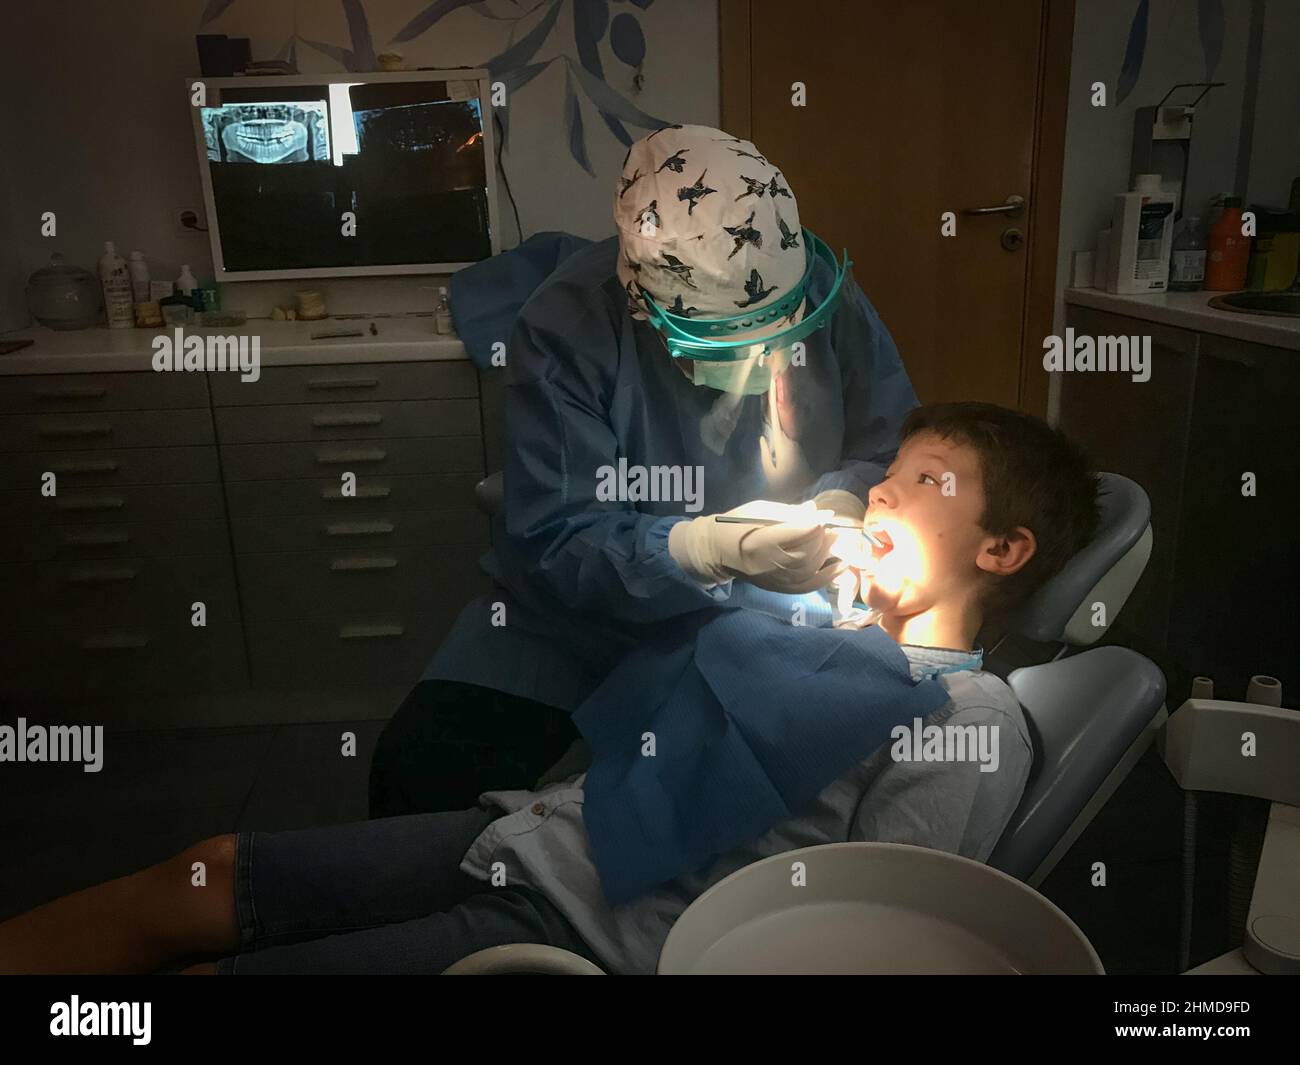

Dentista femmina che indossa un cappuccio floreale che esamina i denti del ragazzo adolescente seduto sulla sedia in clinica dentale Foto Stockhttps://www.alamy.it/image-license-details/?v=1https://www.alamy.it/dentista-femmina-che-indossa-un-cappuccio-floreale-che-esamina-i-denti-del-ragazzo-adolescente-seduto-sulla-sedia-in-clinica-dentale-image491505815.html

Dentista femmina che indossa un cappuccio floreale che esamina i denti del ragazzo adolescente seduto sulla sedia in clinica dentale Foto Stockhttps://www.alamy.it/image-license-details/?v=1https://www.alamy.it/dentista-femmina-che-indossa-un-cappuccio-floreale-che-esamina-i-denti-del-ragazzo-adolescente-seduto-sulla-sedia-in-clinica-dentale-image491505815.htmlRF2KFJ0K3–Dentista femmina che indossa un cappuccio floreale che esamina i denti del ragazzo adolescente seduto sulla sedia in clinica dentale

Dentista femmina che indossa un cappuccio floreale che tiene la bocca del ragazzo caucasico con la mano mentre esamina all'ospedale dentale Foto Stockhttps://www.alamy.it/image-license-details/?v=1https://www.alamy.it/dentista-femmina-che-indossa-un-cappuccio-floreale-che-tiene-la-bocca-del-ragazzo-caucasico-con-la-mano-mentre-esamina-all-ospedale-dentale-image491505756.html

Dentista femmina che indossa un cappuccio floreale che tiene la bocca del ragazzo caucasico con la mano mentre esamina all'ospedale dentale Foto Stockhttps://www.alamy.it/image-license-details/?v=1https://www.alamy.it/dentista-femmina-che-indossa-un-cappuccio-floreale-che-tiene-la-bocca-del-ragazzo-caucasico-con-la-mano-mentre-esamina-all-ospedale-dentale-image491505756.htmlRF2KFJ0H0–Dentista femmina che indossa un cappuccio floreale che tiene la bocca del ragazzo caucasico con la mano mentre esamina all'ospedale dentale

Dentista femmina che indossa cappuccio floreale e guanti chirurgici che esaminano i denti del ragazzo seduto sulla sedia in clinica dentale Foto Stockhttps://www.alamy.it/image-license-details/?v=1https://www.alamy.it/dentista-femmina-che-indossa-cappuccio-floreale-e-guanti-chirurgici-che-esaminano-i-denti-del-ragazzo-seduto-sulla-sedia-in-clinica-dentale-image491505791.html

Dentista femmina che indossa cappuccio floreale e guanti chirurgici che esaminano i denti del ragazzo seduto sulla sedia in clinica dentale Foto Stockhttps://www.alamy.it/image-license-details/?v=1https://www.alamy.it/dentista-femmina-che-indossa-cappuccio-floreale-e-guanti-chirurgici-che-esaminano-i-denti-del-ragazzo-seduto-sulla-sedia-in-clinica-dentale-image491505791.htmlRF2KFJ0J7–Dentista femmina che indossa cappuccio floreale e guanti chirurgici che esaminano i denti del ragazzo seduto sulla sedia in clinica dentale

Dentista che esamina i denti del paziente del bambino piccolo alla clinica Foto Stockhttps://www.alamy.it/image-license-details/?v=1https://www.alamy.it/dentista-che-esamina-i-denti-del-paziente-del-bambino-piccolo-alla-clinica-image460055553.html

Dentista che esamina i denti del paziente del bambino piccolo alla clinica Foto Stockhttps://www.alamy.it/image-license-details/?v=1https://www.alamy.it/dentista-che-esamina-i-denti-del-paziente-del-bambino-piccolo-alla-clinica-image460055553.htmlRF2HMD9FD–Dentista che esamina i denti del paziente del bambino piccolo alla clinica